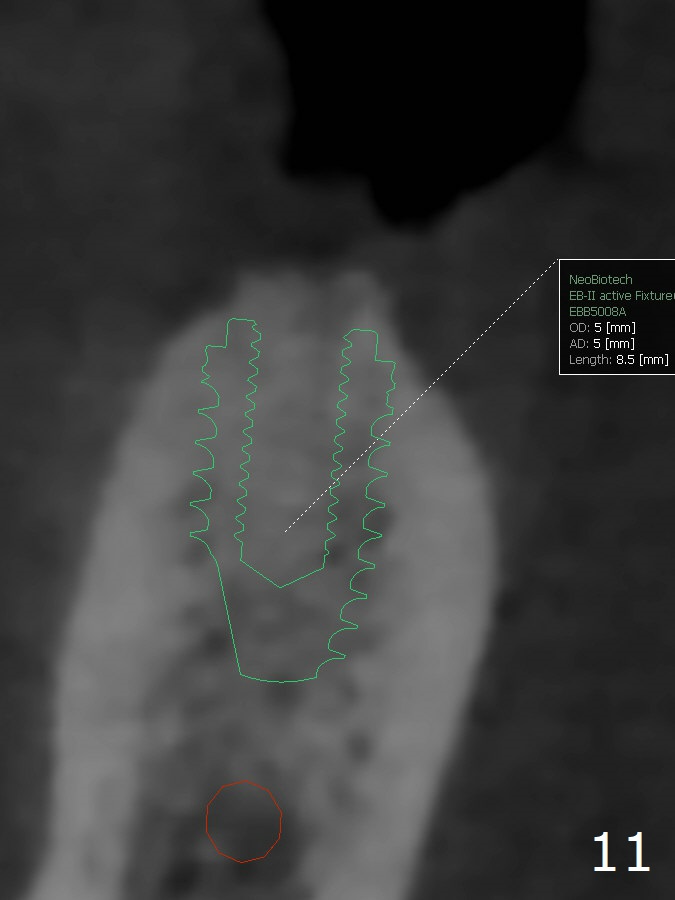

When implants at #4, 13 and 14 are placed, the patient wonders how many more implants are needed. From 0 (considering a lower RPD) to 5 (#3, 19, 20, 25 and 30). The tooth #3 seems to have periodontal-endodontic disease (Fig.1,2). Since the ridge is narrow at #19 and 20 (Fig.3), ridge split at #19 and a 1-piece implant at #20 are planned (Fig.4,5-9). The implant at #19 will be placed in an ideal prosthetic position (Fig.5). The ridge transverse bony cut will be made free hand in the middle (Fig.6,6'), followed by 2 vertical cuts and 1 apical transverse one in the 1st stage of procedure. In order to rotate the buccal block easier (Fig.6 pink curved arrow), the apical transverse cut will be wedge in shape (Fig.6 (red), 6' (double lines), 7 (black)). In the 2nd stage, the ridge top split will be extended by using a chisel (Fig.7 longer red line) and the buccal block will be pushed buccally (Fig.8). A guide will be seated to finish osteotomy (Fig.9 white) and implant placement.

While the ridge at #30 is normal for a normal sized implant (Fig.10,11), the one at #25 is not (Fig.12, a 2 mm 1-piece implant).